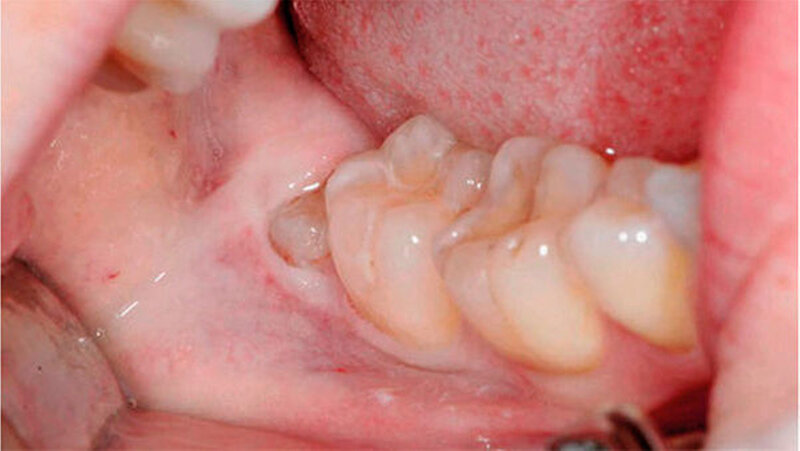

Bei der 27-jährigen, gesunden Patientin, kam es zu rezidivierender Perikoronitis des teilretinierten Zahns 48 (Abb. 1a). Primär wurde eine OPT-Aufnahme zur Operationsplanung erstellt (Abb. 1b). Dabei zeigte sich eine komplette Überlagerung der Zahnwurzel über den C. mandibulae. Zur weiteren Abklärung der Lagebeziehung wurde eine DVT-Aufnahme erstellt (Abb. 1c). Eine linguale Lage des C. mandibulae zur Zahnwurzel konnte festgestellt werden. Eine knöcherne Begrenzung des C. mandibulae zur Zahnwurzel fehlte.

Aufgrund des hohen intraoperativen Läsionsrisikos für den N. alveolaris inferior wurde eine Koronektomie geplant; die Patientin willigte nach eingehender Aufklärung ein. Präoperativ spülte sie mit 0,2 Prozent Chlorhexidin-Mundspülung (Curasept ADS® 220, Curaden AG, Kriens, Schweiz). Eine Leitungsanästhesie des N. alveolaris inferior sowie eine Infiltrationsanästhesie bukkal wurden durchgeführt (Ultracain ds forte, Sanofi-Aventis AG, Vernier, Schweiz).